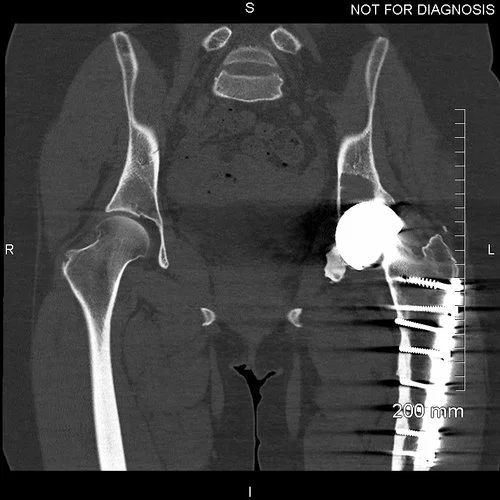

Coronal CT - This is used by the surgeon and the biomedical engineer to design the custom implant specifically to the patient’s acetabular bone stock. This CT demonstrates significant loss of bone stock relating to the left hip resurfacing.

3D CT reconstruction showing the hemipelvic defect.